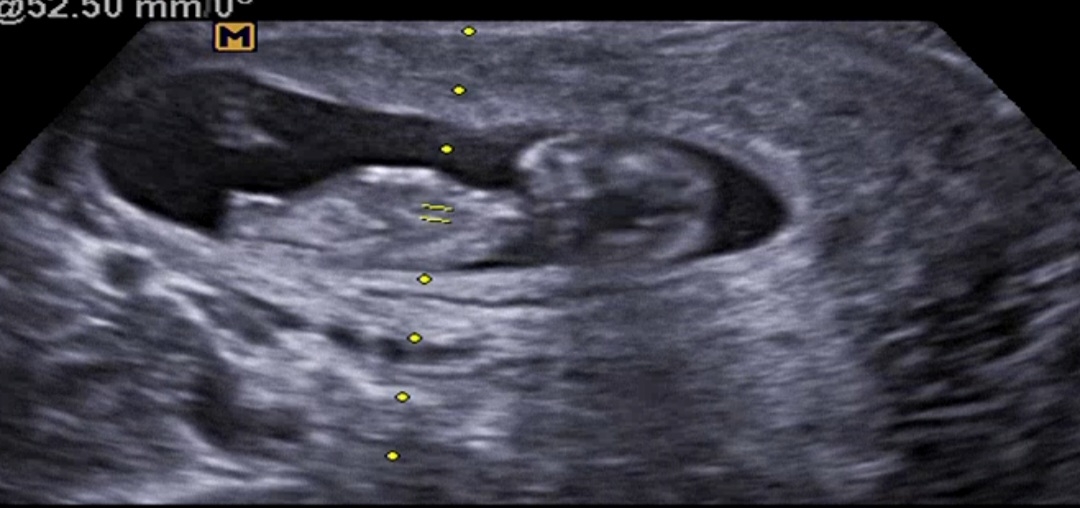

각도법! 딸맞는지봐주세요

사진이 한장밖에 안올라가네요 ㅠㅠ? 딸같은데 다른분들이 보시기에도 그런가요~? 캡쳐를 잘못했으면 말씀해주시면 다른사진으로 올려볼게요!!

딸 한표오!

딸같아용!

저도 초음파 저런 모습이었는데 딸이었어요!!☺️